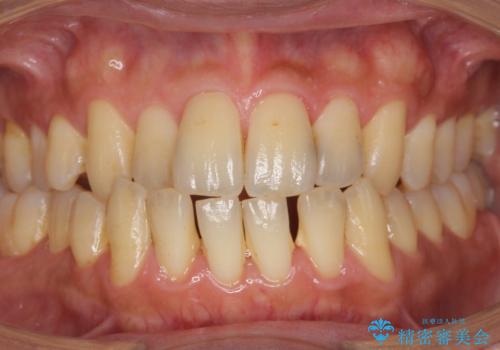

前歯のセラミック治療

- 左の前歯が黒いとのことで来院。

1番目の歯は小さい虫歯があったのでプラスチックの樹脂で治療をしました(保険内)。

2番目の歯は二箇所虫歯があり、プラスチックの樹脂で治療するとつぎはぎみたいになってしまうので、

白い被せ物(ジルコニアクラウン)で治療しました。

自然な被せ物が入り、大変満足して頂けました。